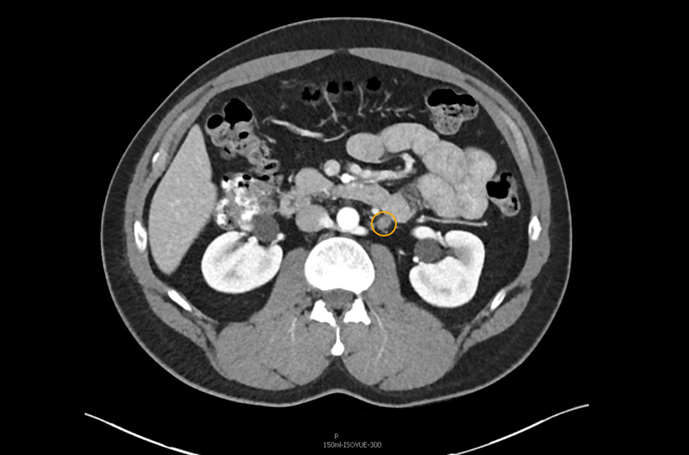

The patient was appropriately managed with active surveillance. Six months following orchiectomy, surveillance CT imaging demonstrated two enlarged para-aortic lymph nodes measuring 1.5 cm, consistent with metastatic disease (Figure 1). CT of the chest remained negative, and serum tumor markers continued to be within normal range.

The patient underwent primary RPLND without complications. A bilateral dissection template with right nerve-sparing was performed (Figure 2). The procedure was completed through an upper midline incision, with an operative time of approximately five hours and an estimated blood loss of 100 mL.